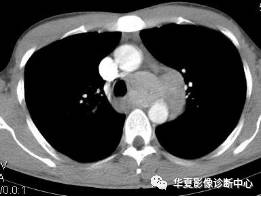

男性,32岁。无明显原因胸闷不适3月,胸片示纵隔及左肺门占位。

【CT征象】纵隔主肺动脉窗内见团状软组织肿块,最大截面约5.0cmX4.0cm,密度均匀,动脉期呈中度强化,延迟扫描呈明显强化,接近同期血管密度;左肺动脉干及左主支气管略受压。

【CT诊断】 ①巨淋巴结增生症;②淋巴瘤;③结节病;④淋巴结结核。

【最后诊断】纵隔巨淋巴结增生症。